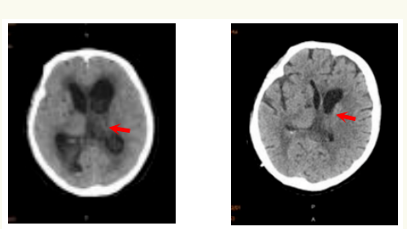

我科与“付继弟颅内感染诊疗团队”进行了密切合作,成立了“中枢神经系统感染诊治中心”,已经成功开展了各种原因引起的颅内、椎管内顽固性严重感染性,和相关神经重症疾病的诊断与治疗,收治的病人来自京外各地医院转来的重症患者。付继弟教授、潘栋超医生亲自参与我科病人的手术及围手术期管理和诊疗工作,经治疗的患者病情均得到有效的转规,好转出院。

我科与首都医科大学附属北京胸科医院建立技术合作,联合“付继弟颅内感染诊疗团队”共同组建了由张立群教授、付继弟教授、张蓬川主任医师、潘栋超和何刚副主任医师组成的“中枢神经系统结核病诊疗团队”,成立了“中枢神经系统结核病诊治中心”,形成了针对“中枢神经系统结核性疾病”的内外科全面系统的诊断及治疗体系,病情均得到有效治疗,病人好转出院。